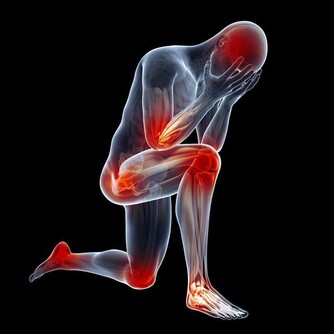

臨床上經常遇到久治不癒的“關節炎”、“肩周炎”,

對症治療暫時見效後又迅速復發,甚至症狀加重,最後診斷都是肺癌。

既然是肺癌,為何沒有肺部症狀,反而會是關節痛呢?

有文獻報導認為,癌細胞在增生分化過程中,會引起生長激素分泌異常。

大量的生長激素會刺激骨關節異常增生,侵犯膝、踝、腕等大關節,出現腫脹、疼痛等症狀。

據報導,老年人肺癌合併關節痛的發生率約佔10%至20%。